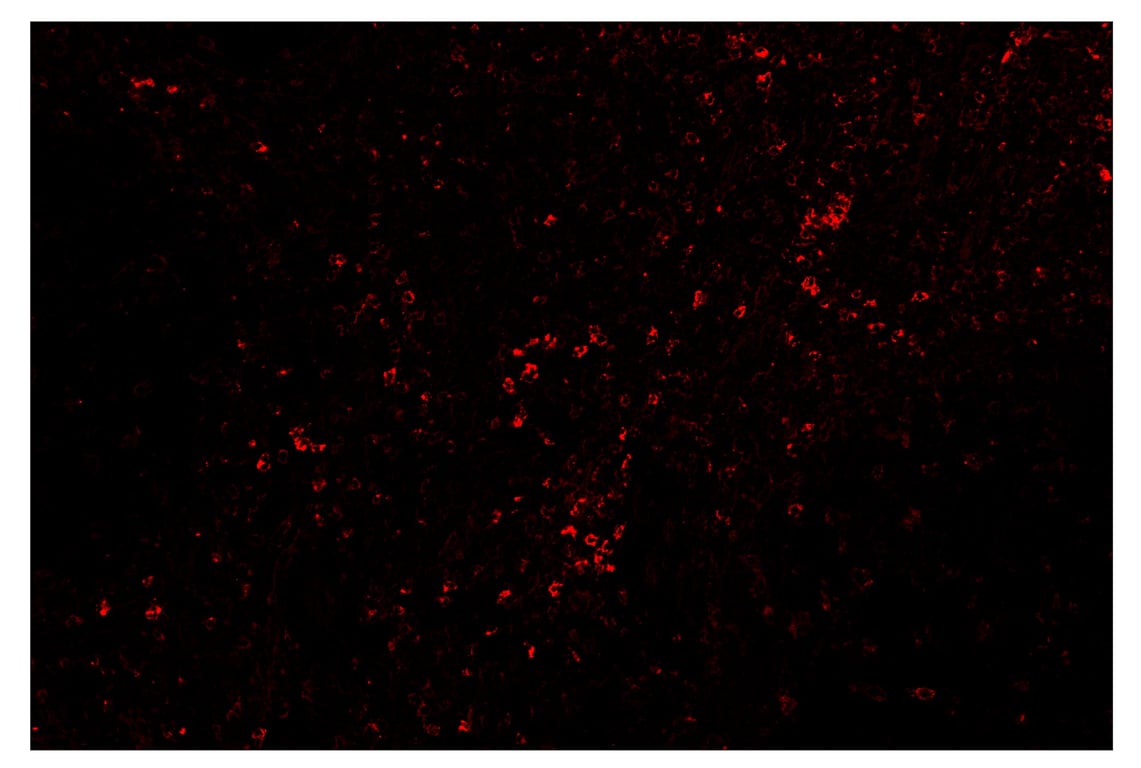

SignalStar™ immunohistochemical analysis of paraffin-embedded human tonsil using TIM-3 (D5D5R™) & CO-0010-647 SignalStar™ Oligo-Antibody Pair #15231 (red). All fluorophores have been assigned a pseudocolor, as indicated. Staining was performed on the BOND RX by Leica Biosystems.

Immunohistochemistry Image 4: TIM-3 (D5D5R<sup>™</sup>) & CO-0010-750 SignalStar<sup>™</sup> Oligo-Antibody Pair